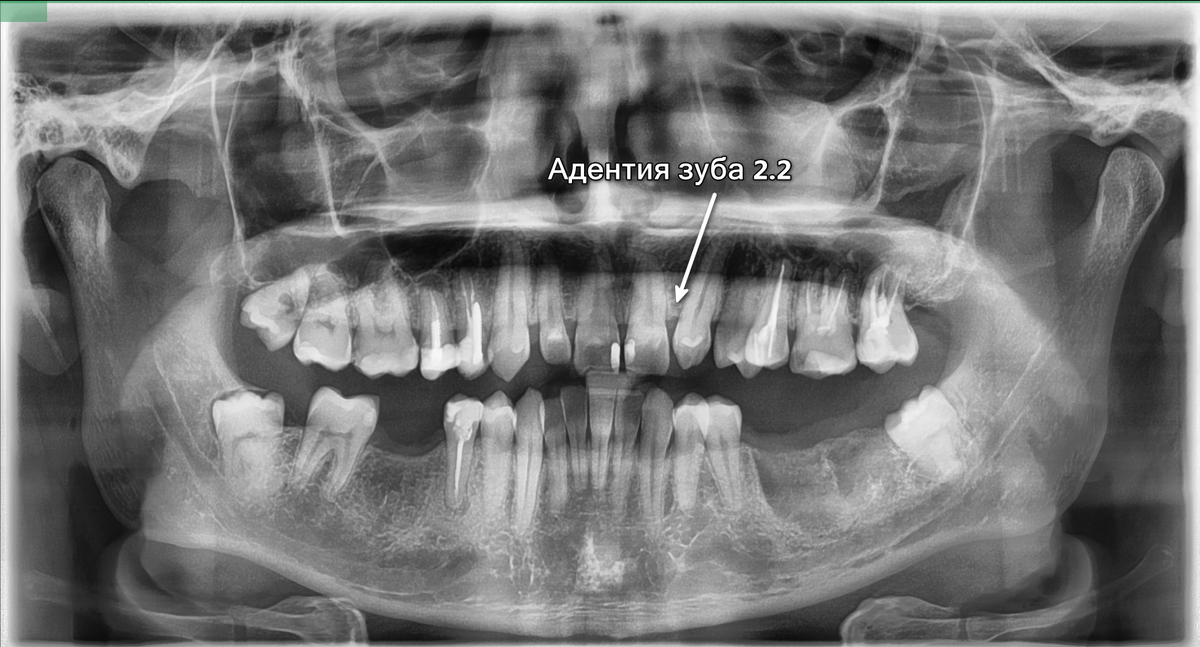

У пациента была первичная генетическая проблема — адентия зуба 2.2. Зачаток не сформировался и зуб не прорезался. Остальные проблемы вызваны недостаточным качеством ухода за полостью рта и несвоевременным лечением. Из-за отсутствия терапевтического лечения кариес перешел в пульпит, после чего развилось воспаление костной ткани в результате периодонтита.

Первичная адентия — зуб 2.2 отсутствует, на его место передвинулся клык 2.3